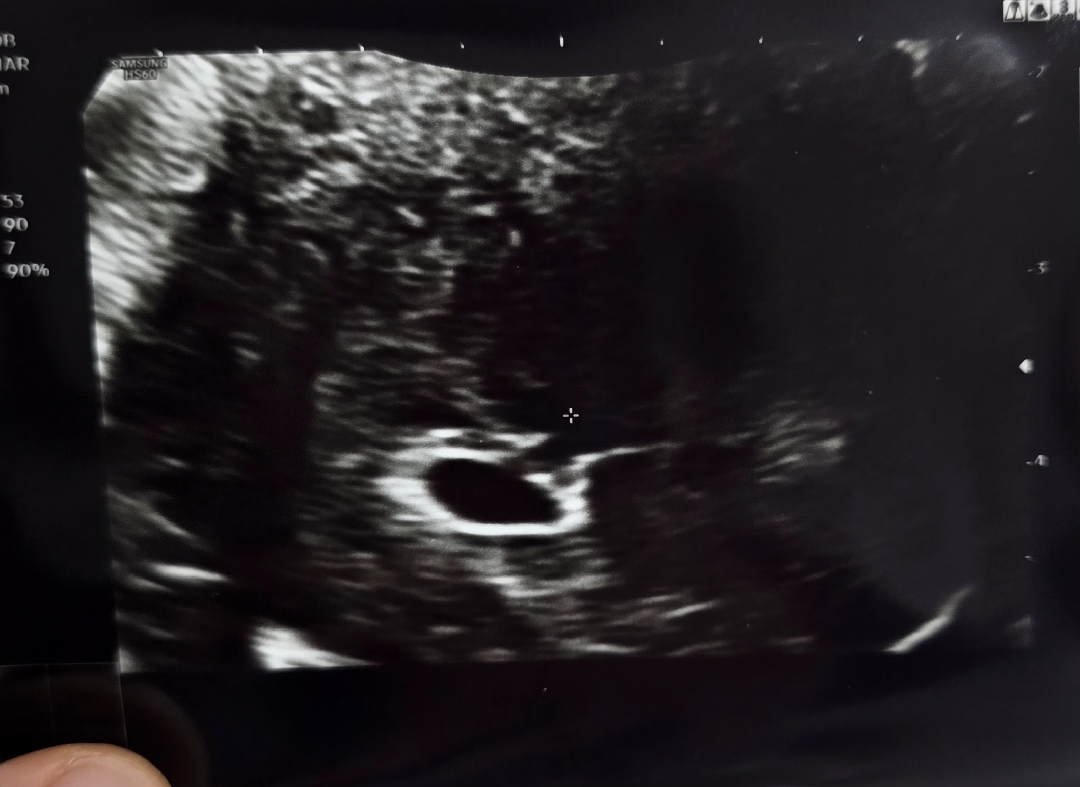

아기집보고 왔어요~

막생 7월5일이구 8월2일에 임테기 두줄봤다가 8월 4일에 피검사수치 238 나와서 오늘 다시 병원갔다가 아기집보고 왔어용 원장님 말씀으로는 4주 추정이라는데 원래 아기집만 덩그러니 있는게 맞나여 ㅋㅋㅋ 첨이라 모든게 다 걱정...ㅎ

첨엔 아기집만 보이는게 정상이예여! 저도 첫 촘파에 아기집 1센치만 보엿구 그 담 촘파에서 난황까지 확인햇어요! 돌아오는 토요일에는 심장 뛰는 소리 들으러 감니당..💗